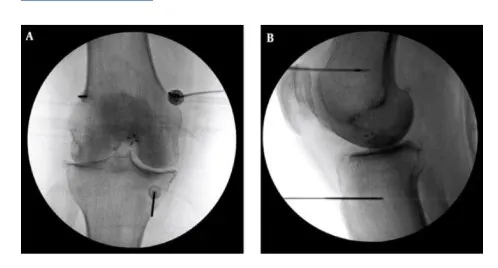

高頻熱凝療法以X光定位將電極導針導引至膝蓋的三個主要感覺神經叢,藉由熱能與電效應,麻痺痛覺神經。(台北慈濟醫院提供)

李宜軒說明:「此項技術過往多用於椎間盤突出、滑脫等脊椎神經壓迫造成的下背痛、坐骨神經痛的止痛治療,近來也運用至膝關節退化。執行方式是在局部麻醉的情況下,以X光定位將電極導針導引至膝蓋的三個主要感覺神經叢,確認施行目標後,接上電源線輸出高頻電波,藉由熱能與電效應,使引起疼痛的神經失去傳導疼痛的能力,降低疼痛。」一般而言,效果會在術後當下或1週內顯現,普遍可維持半年1到兩年,因人而異。但若有急性感染、心律調節器或正在服用抗凝血劑者即不適用此治療,需由醫師進行評估。